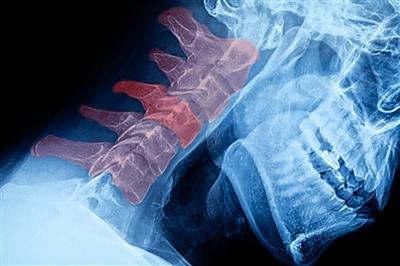

The most common symptom of tech neck is, of course, neck pain and discomfort, but you might notice other aches and pains too. Headaches, shoulder pain, neck spasms and weakness or tingling in your arms as a result of a pinched nerve can also be a result of tech neck. Long term, your positioning can also cause a herniated disc or affect the curvature of your spine.